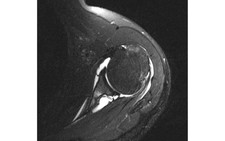

Điều trị hội chứng đau vùng cổ vai - Ảnh: BS HỒ NGỌC LIỂNG

Chị N. được các bác sĩ chẩn đoán bị hội chứng đau cổ vai và được điều trị bằng phương pháp cấy chỉ.

Các bác sĩ đông y thường dùng phương pháp cấy chỉ để trị bệnh. Cấy chỉ (nhu châm) là phương pháp đưa đoạn chỉ tự tiêu (làm bằng protein) vào trong huyệt, nhờ tác dụng kích thích huyệt liên tục làm khí huyết lưu thông, giảm đau, giảm co cứng cơ.